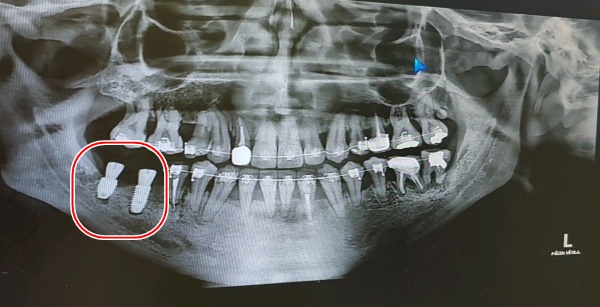

거즈를 물라고 하고 수술이 잘 됐는지 확인차 엑스레이 한번 찍고

다시 또 작업하고, 또 엑스레이 실로 가고를 1번 반복 후 이제 거의다 됐다면서

어금니쪽이라 임플란트를 좀 큰 걸로 한건지는 모르겠으나 왜이리 커보이는지;;